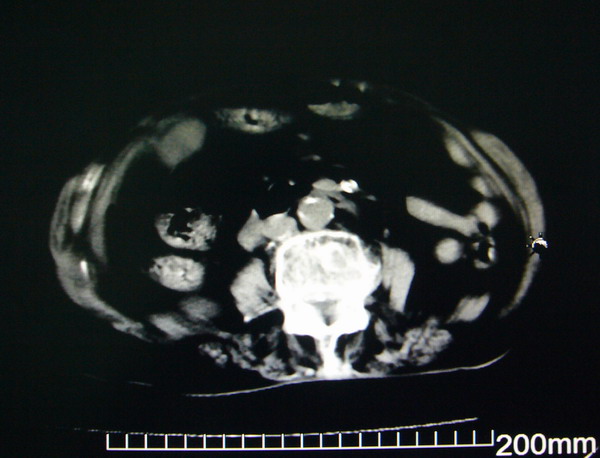

女:83y,转移性右下腹痛2小时,白细胞计数增高。

1.右侧肾盂扩大,肾盏无扩张,考虑:先天性肾盂变异可能性大。

2.胆囊扩张,考虑:胆囊炎。

3.阑尾区域可见以结节样高密度影,结合病史,考虑:阑尾结石,阑尾炎。

右下腹肠系膜增厚,结合病史支持阑尾炎.

右侧壶腹型肾盂可能,建议输路造影或增强

1.右侧肾盂扩大,考虑先天性肾盂变异或肾盂旁囊肿。

2.胆囊扩张,考虑胆囊炎。

3.阑尾区域可见结节样高密度影,结合病史考虑:阑尾结石、阑尾炎。